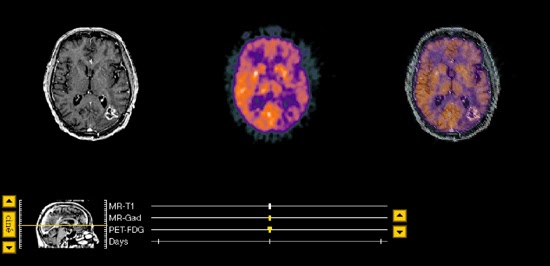

The T1-weighted precontrast MR(not

shown) demonstrated an area of low signal intensity throughout the left

parietal-occipital area which was new. A previous study had shown only

postoperative changes. Following the administration of contrast material(gadolinium-DTPA), signal intensity was much enhanced, as seen in image 59 and

surronding slices, suggesting either tumor recurrence or radiation necrosis.

This finding also represented a change when compared to the previous contrast

enhanced MR. The PET scan demonstrated high activity in this region, suggestive

of tumor recurrence, and effectively ruling out radiation necrosis.